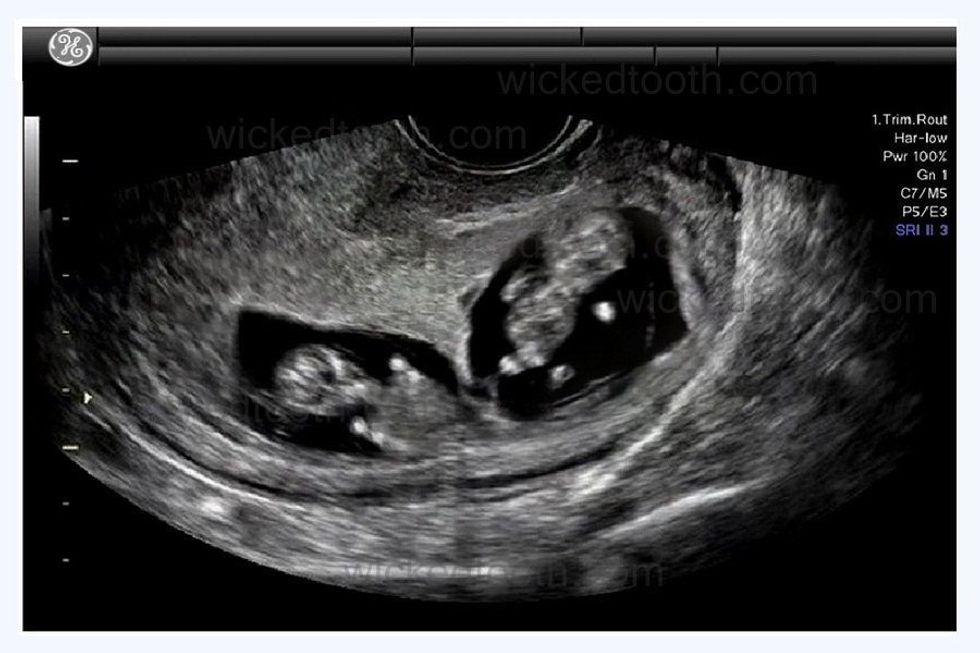

Nëse vezoret e një gruaje në të njëjtën kohë lirojnë dy vezë gjatë periudhës së ovulacionit, atëherë binjakët janë vëllazërore. Ata nuk do të jenë “si dy pika uji", por si çdo vëlla e motër.

Në të kundërt monozigotë/binjakët identikë vijnë nga një vezë, e cila është e ndarë në dy dhe ngjashmëria e tyre është e pabesueshme.